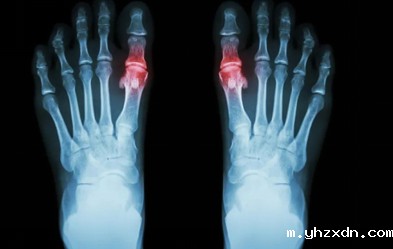

上海bet必威网址:如何预防痛风?需要避免的食物有哪些?

上海bet必威网址如何预防痛风

足量饮水。保持充足的水分,主要是通过大量饮水。含糖饮料尽量少喝,尤其是含有高果糖玉米糖浆的饮料。

限制或避免饮酒。与您的上海bet必威网址医生讨论是否您饮用的酒精数量或种类对健康安全)。最近的证据表明,啤酒较易诱发痛风发作,尤其是对男性。

从豆类、鸡蛋和低脂奶制品中获取蛋白质。低脂乳制品实际上可以预防痛风的发生,对降低痛风发作有一定作用,是痛风患者的优质蛋白质来源。

限制肉类、鱼类和家禽的摄入。可以少量摄入,但要密切注意哪种肉类、摄入多少量的情况可能会给你带来问题。

增加锻炼的频率和强度。运动不仅有助于减肥,还能降低尿酸水平。

保持理想体重。超重可能导致胰岛素抵抗,导致出现尿酸升高。不过,减轻体重应循序渐进,否则容易导致酮症或痛风急性发作。

上海bet必威网址提醒需避免的食物

高嘌呤的食物(100克含有超过150 - 200毫克嘌呤)可能会提高你的尿酸水平。这些包括:

• 动物脏器——肝、心、肾和脑

• 一些红肉—牛肉、羊肉等和野味,如鹿肉

• 鱼——鲱鱼,鳟鱼,鲭鱼,金枪鱼,沙丁鱼和凤尾鱼(鲑鱼除外,与其他鱼类相比,鲑鱼含有较低水平的嘌呤)

• 海鲜——虾、扇贝、螃蟹和鱼籽

• 酒精——尤其是啤酒

• 含糖饮料——碳酸饮料、果汁和风味热饮或冷饮

• 甜味剂——高果糖玉米糖浆

• 酵母——营养酵母、啤酒酵母以及其他酵母补充剂